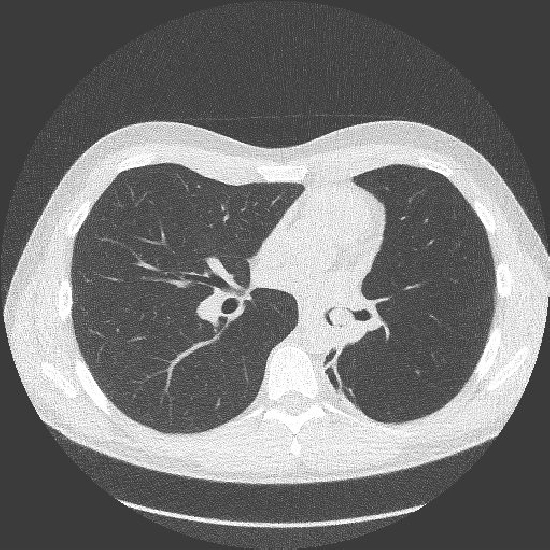

2. Um was für eine Untersuchungstechnik handelt es sich?

- d) CT

4. Welchen Befund beschreiben Sie bezüglich der Lungen?

- c) Raumforderung im rechten Unterlappenbronchus

5. Sofern nicht bereits erfolgt, welche weitere Diagnostik veranlassen Sie?

- a) Bronchoskopie